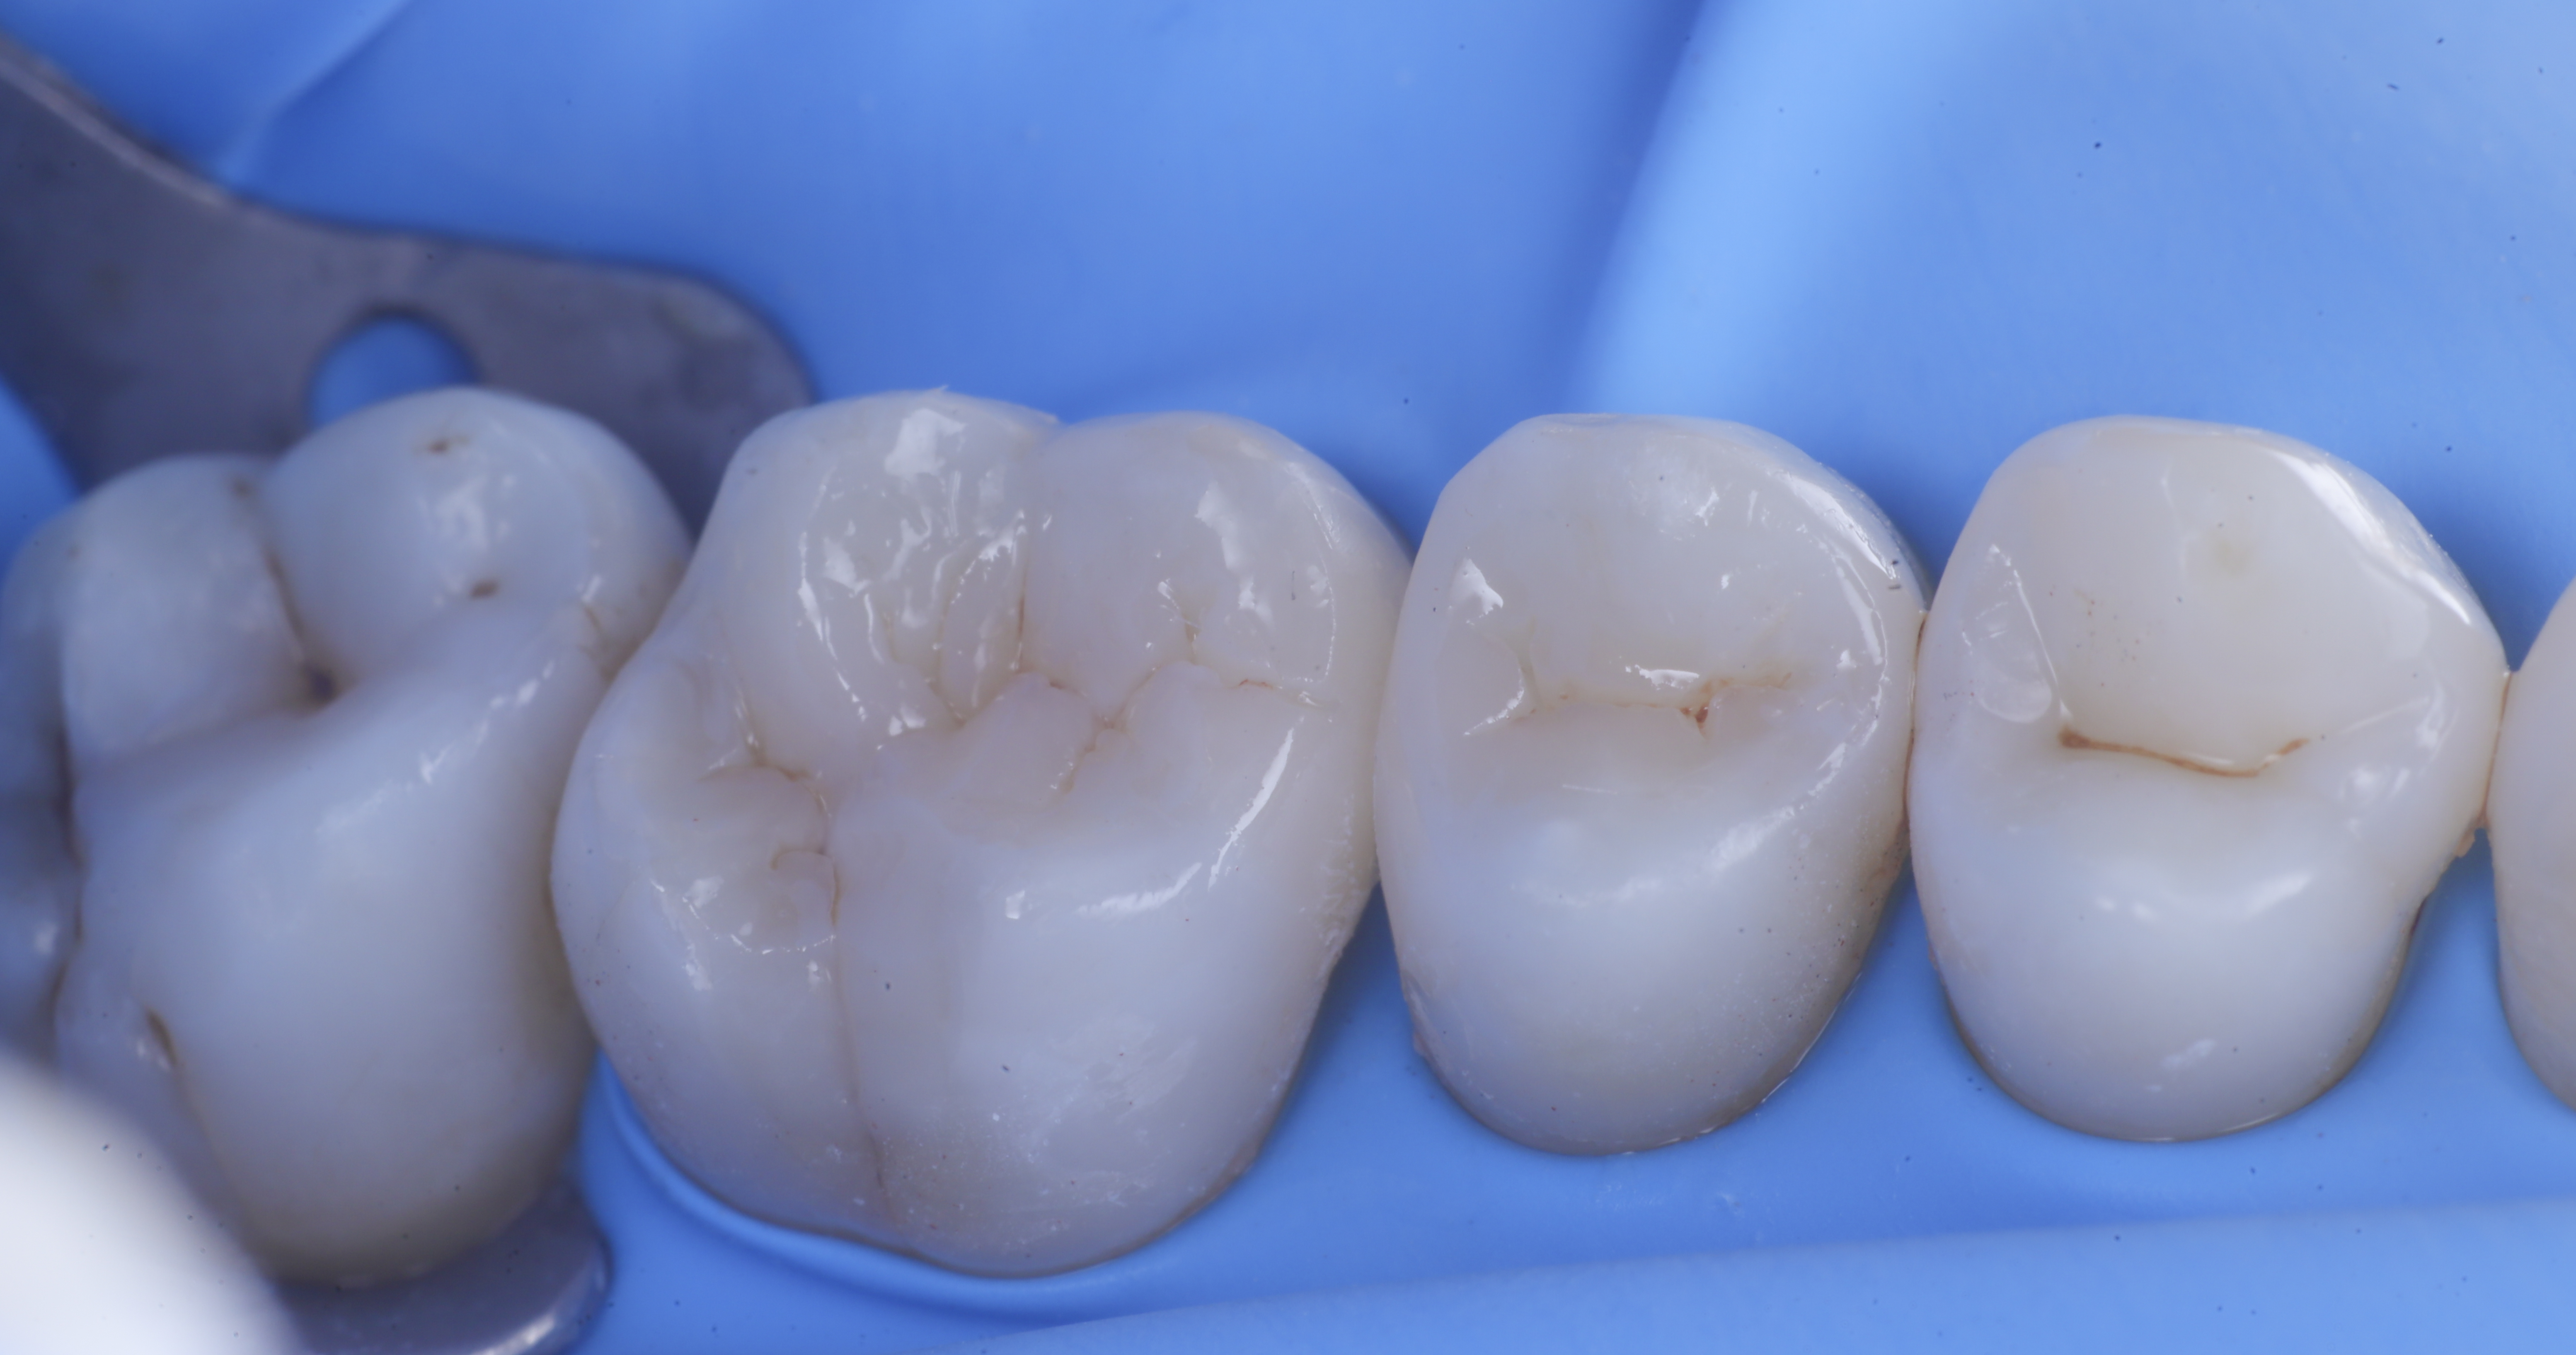

foto 8 Modellazione ed aspetto occlusale

foto 9 Modellazione ed aspetto vestibolare

foto 10 Modellazione ed aspetto palatino